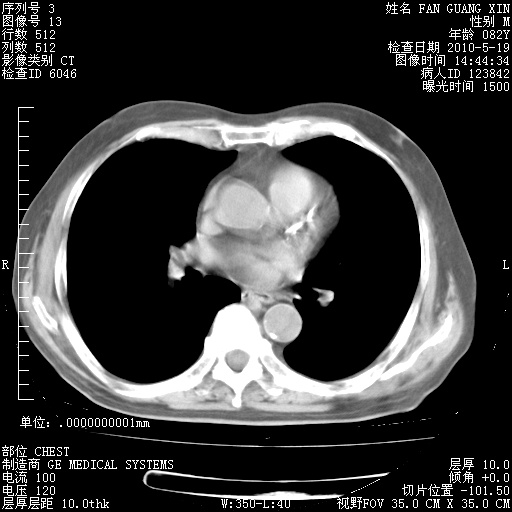

复查肺部CT,明显好转。为什么发热呢?

治疗3周后的肺部CT

治疗3周后的肺部CT纵隔窗